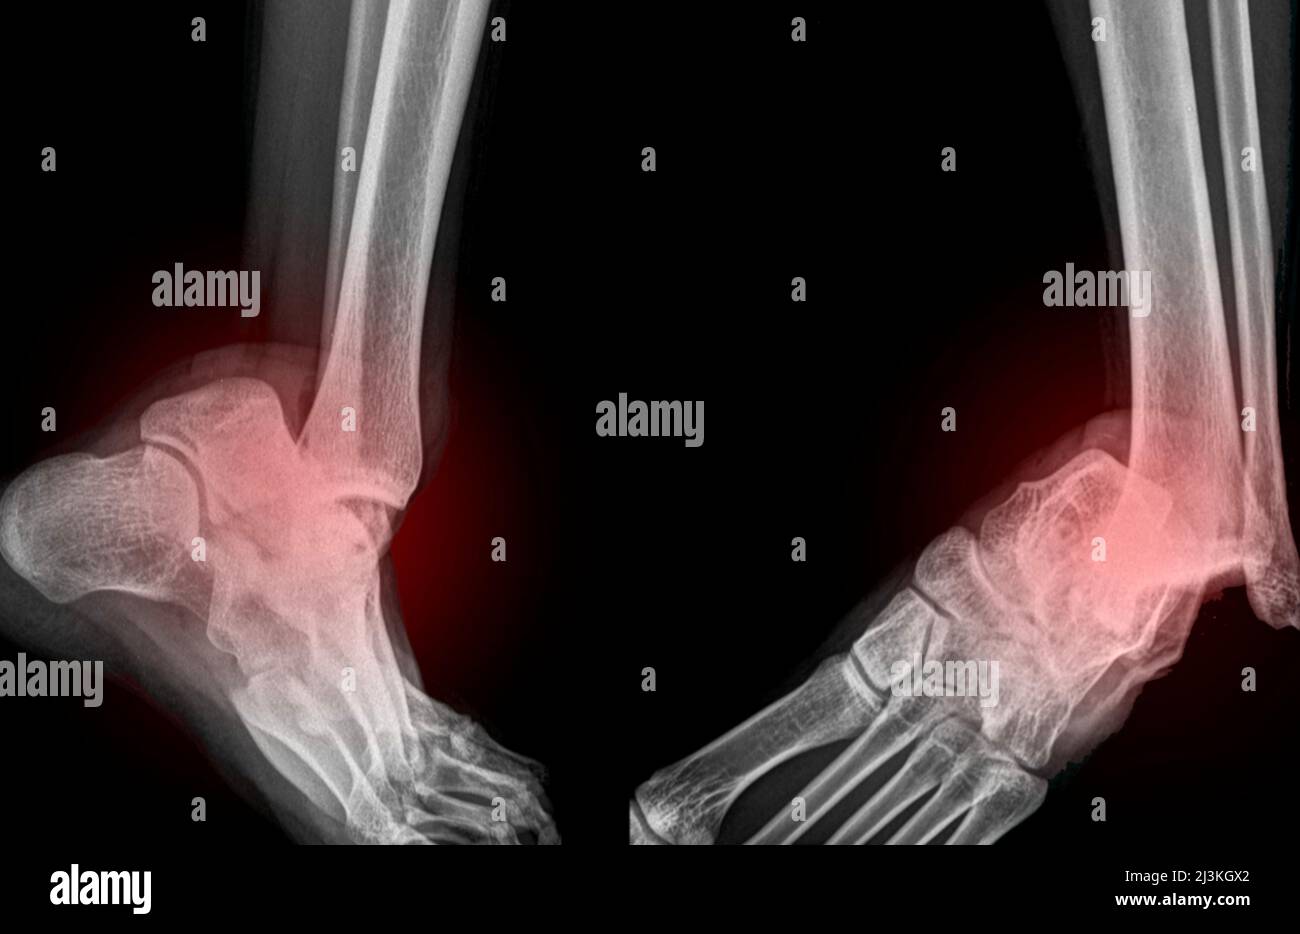

from es.dreamstime.com

Tobillo dislocado, rayos X Fotografía de stock Alamy Como Se Ve Un Tobillo Dislocado Una dislocación es una lesión que hace que los huesos de una articulación se salgan de posición. La causa suele ser una caída o un golpe y, algunas veces, una consecuencia de practicar un deporte de contacto. ¿cómo se diagnostica la dislocación del tobillo? La dislocación del tobillo es una lesión común que ocurre cuando los huesos del tobillo se. Como Se Ve Un Tobillo Dislocado.